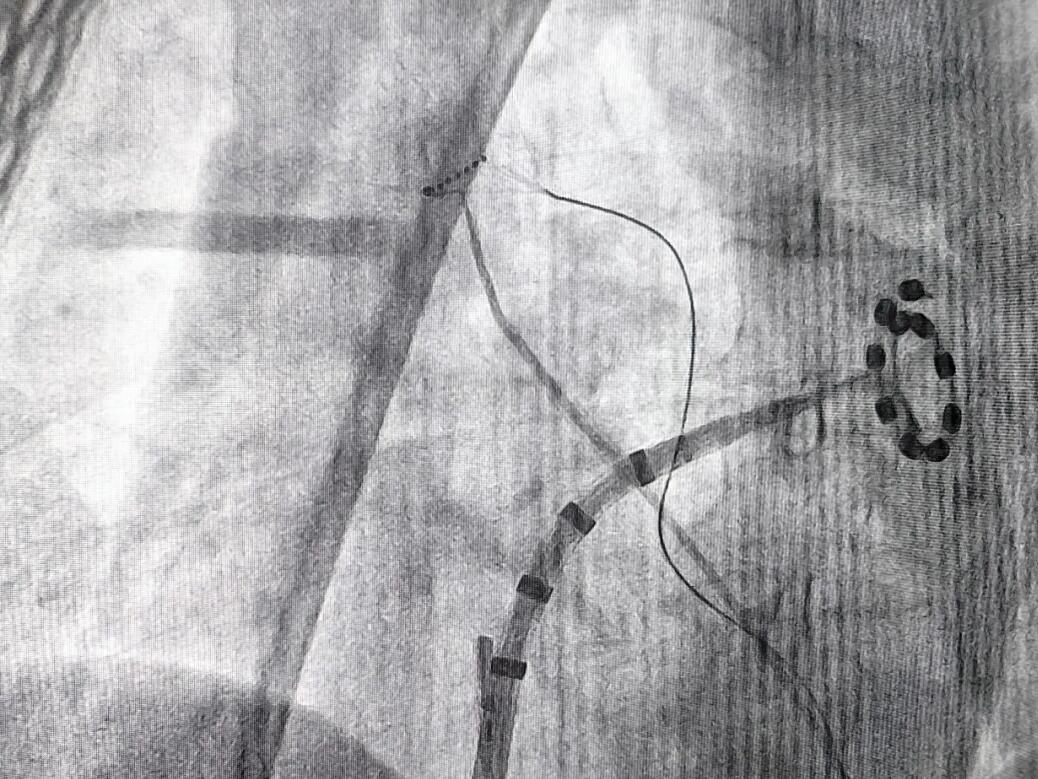

2026年3月18日深夜,轮台县人民医院介入中心的显示屏上,心脏三维模型正随着心跳精准转动。70岁的努尔尼沙汗·买买提平静地躺在手术台上,她不知道的是,自己正在经历的这场“三维脉冲消融术(PFA)”,不仅是巴州县域首例房颤脉冲消融手术,更开创了县级医院治疗复杂心律失常的新纪元。

“手术仅用了30分钟。”李耀东教授走下手术台时说,“脉冲消融是一种全新的能量形式,能够选择性损伤心肌组织,对周围食道、血管零损伤。这项技术即使在首府的大医院也算前沿,如今在轮台实现了‘技术平移’。”

这是一场含金量极高的“技术博览会”,六台手术涵盖了脉冲消融术(PFA)、射频消融术+左心耳封堵术及心脏起搏器植入术等全类型技术。曾经,县域患者面对心律失常,要么长期服药忍受不适,要么远赴千里之外求医。而如今,从最基础的起搏器到最前沿的脉冲消融,轮台县人民医院实现了心律失常介入技术的“全覆盖”。